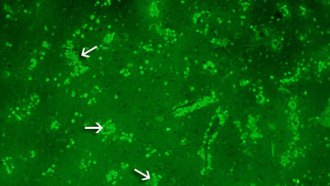

Pills of frozen poop fight killer disease

Popping poop pills? Of course it sounds yucky. But researchers find it might just be one of the most effective ways to knock out a very serious — and tough-to-kill — intestinal disease.